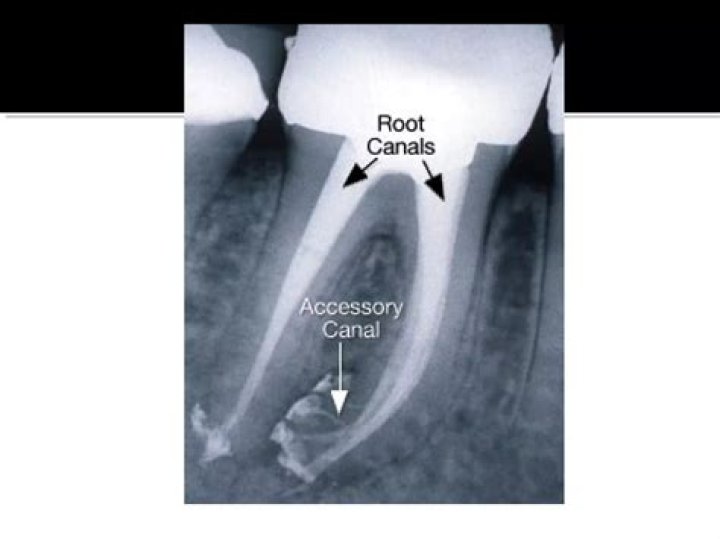

Can xray show if you need root canal?

When you get an x-ray, this will give definitive proof that you need to get a root canal. The x-ray gives the dentist a clear view of any infection in the tooth especially one at the root of the tooth.